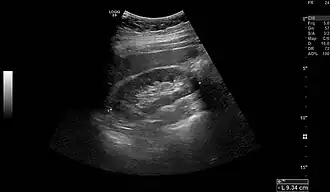

Normal adult right kidney as seen on abdominal ultrasound with a pole to pole measurement of 9.34 cm

A Danish study measured the median renal length to be 11.2 cm (4+7⁄16 in) on the left side and 10.9 cm (4+5⁄16 in) on the right side in adults. Median renal volumes were 146 cm3 (8+15⁄16 cu in) on the left and 134 cm3 (8+3⁄16 cu in) on the right.[17]